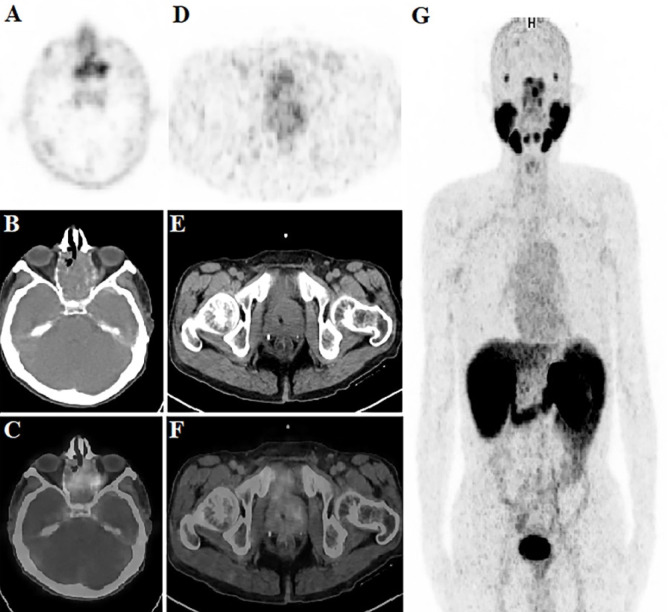

A rare tumor, intestinal-type adenocarcinoma (ITAC), accounts for 8-25% of all sinonasal malignancies. The tumor's histological resemblance to gastrointestinal tract adenocarcinoma is implied by its name. ITAC develops in the ethmoid sinus and upper nasal cavity. Herein, we present sinonasal ITAC with increased prostate-specific membrane antigen expression and fluorodeoxyglucose uptake.